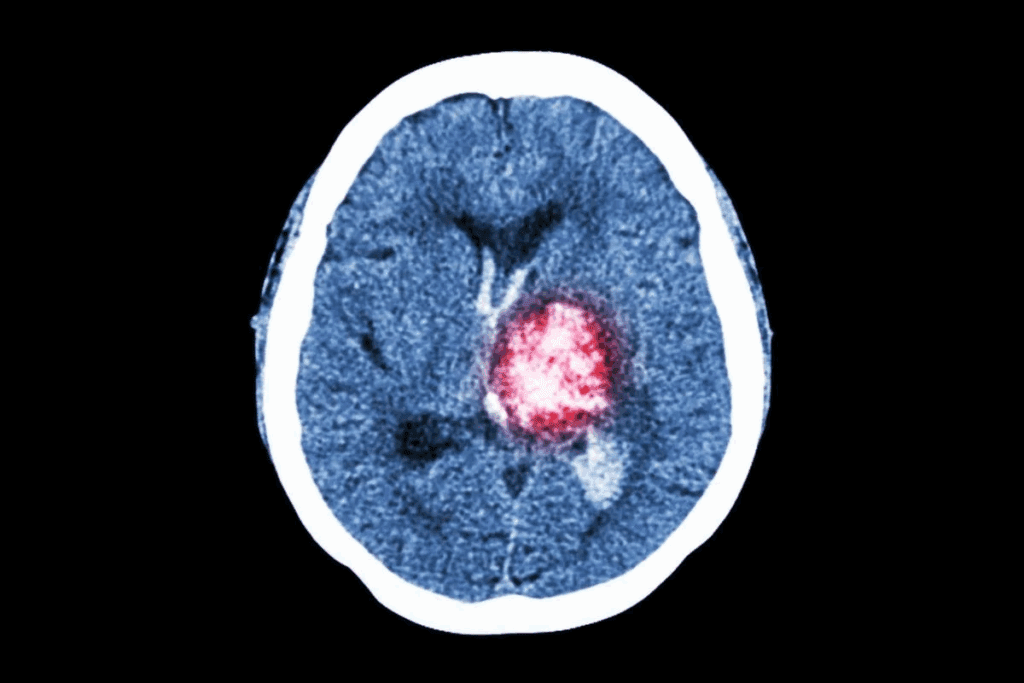

Brain and Central Nervous System Tumors

Brain and CNS tumors are the second most common in kids. They can happen in different parts of the brain and spinal cord. Medulloblastoma and gliomas are common types. Genetic conditions like neurofibromatosis can increase the risk.

“The development of brain tumors in children is often associated with genetic predisposition and certain environmental exposures.” – Expert in Pediatric Oncology

Medical tests are essential for diagnosing childhood tumors. MRI and CT scans show where and how big the tumor is. They also check if it has spread.